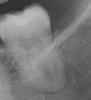

retarded Опубликовано 22 ноября, 2009 Поделиться Опубликовано 22 ноября, 2009 (изменено) Уважаемые доктора!Подскажите план действий. Есть вот такое чудо-юдо во рту, №8 слева снизу. Вид не очень презентабельный но ведет себя тихо. Хочется через соседа, т.е. на место убитой 6-ки вставить имплант (не с одновременным удалением, а погодя, т.к. организм-зараза не любит антибиотики). Имплантолог об опасности не сказал, но почитав самостоятельно, догадываюсь, что может и этого красавца заодно удалить попутно с 6-кой, дабы расчистить от заразы "зону имплантации". Или лучше не стоит, и так зубов немного - поберечь бы? Тем более что гражданин какой-то капризный - с карманами и капюшонами - что еще выкинет при удалении? Не придется ль глотать антибиотики? Изменено 22 ноября, 2009 пользователем retarded Ссылка на комментарий

Bier Опубликовано 22 ноября, 2009 Поделиться Опубликовано 22 ноября, 2009 не ищите себе проблем, нормальный зуб. Ссылка на комментарий